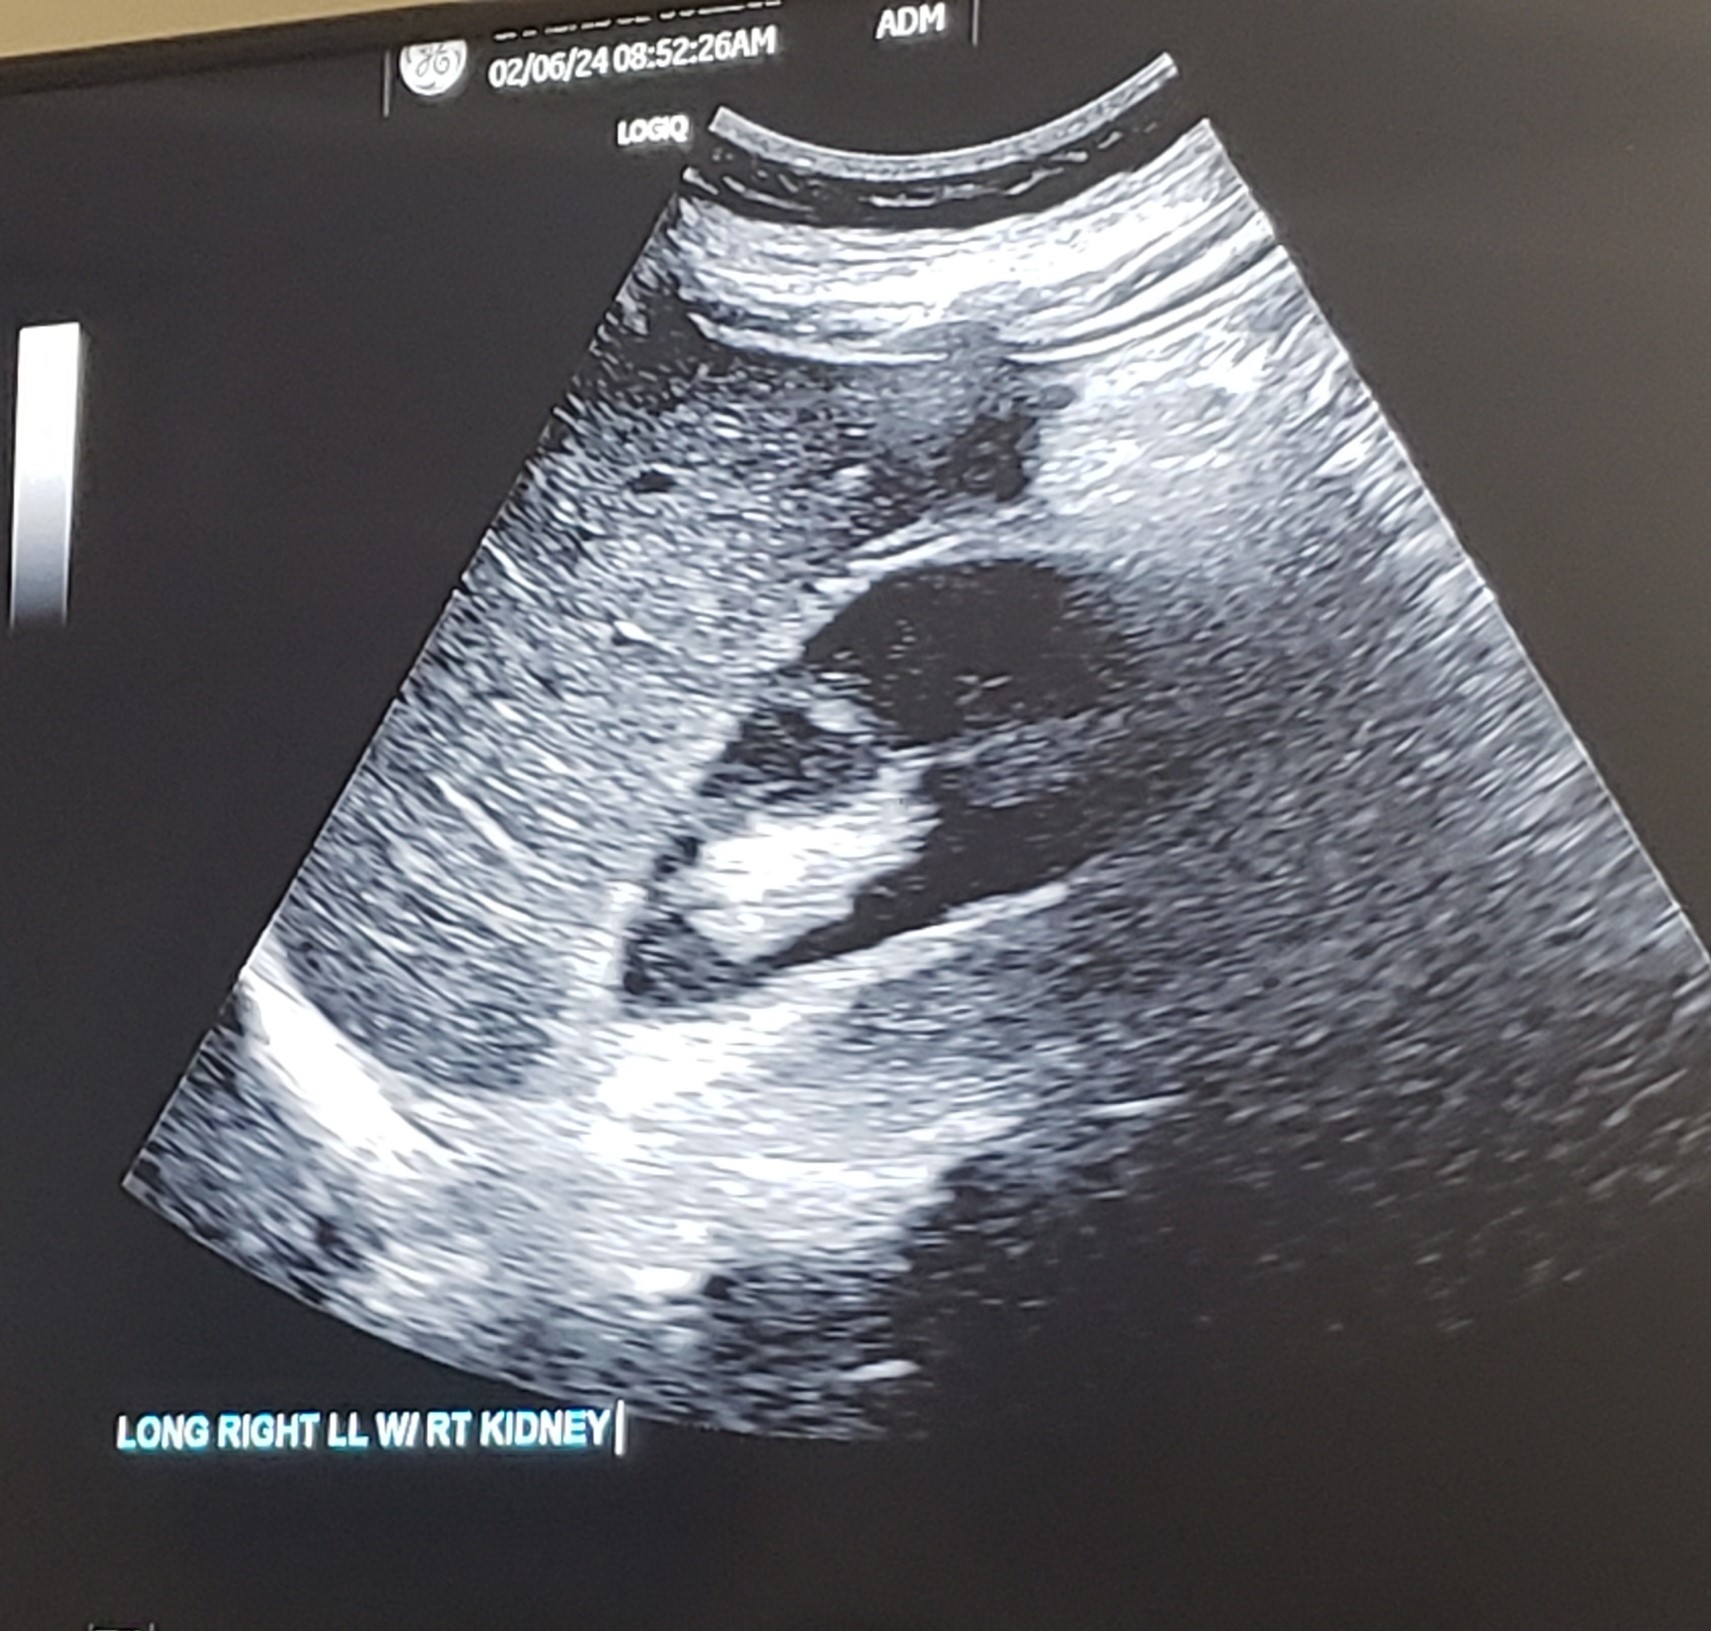

Sag./Long RLL w/ Rt. Kidney interface

Sag./Long RLL w/ Rt. Kidney interface w/ measurement